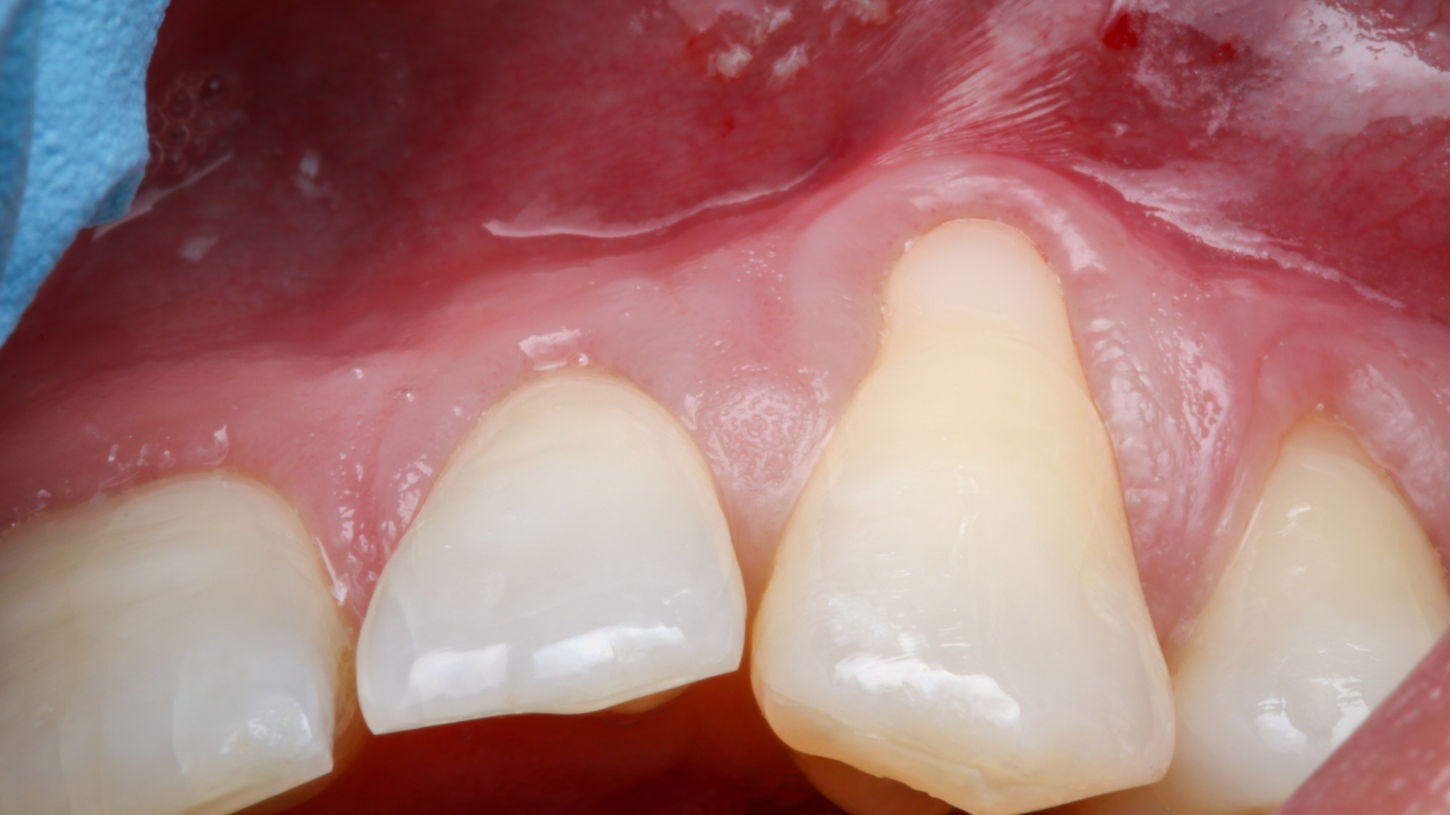

This gingival graft case at SOL Dental Arts in Maspeth, Queens addresses recession around a canine tooth with soft tissue treatment designed to improve root protection, reduce sensitivity concerns, and enhance gumline appearance. When gum recession exposes the root surface, the issue can be both functional and cosmetic. A grafting procedure may be recommended to strengthen the area, improve tissue coverage, and create a more stable, natural-looking gum contour. This type of case is especially important when the patient wants to address recession early and protect long-term periodontal health while also improving smile esthetics.

Evaluation of canine recession

Periodontal soft tissue grafting procedure

Root coverage and gumline contour improvement